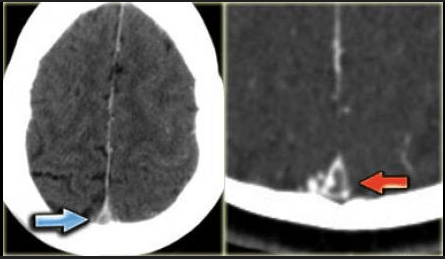

The name of this sign which can indicate a dural venous sinus thrombosis.

What is Delta Sign?

This is the finding on this CT.

What is subarachnoid hemorrhage?